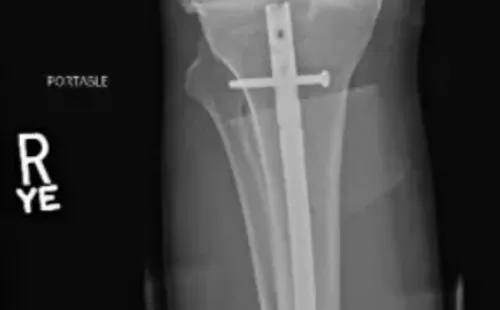

A través de su cuenta de Twitter, el artista marcial compartió imágenes del proceso que se llevó a cabo para reconstruir su pierna. En ellas se pueden ver la barra de titanio que se le dejó para afirmar sus huesos, además de los tres tornillos que fijaron la placa.

Luego de la intervención. Foto: Twitter

Weidman terminó con un fierro y tres tornillos. Foto: Twitter